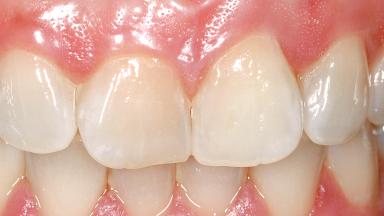

Immediate Flapless Placement of an Implant in a Maxillary Left Central Incisor Site

A 29-year-old female patient presented for treatment to replace the upper left central incisor tooth with an implant- supported restoration. The tooth had been intermittently symptomatic for the previous 12 months. The tooth had originally suffered trauma about 15 years previously. Several endodontic treatments had been performed, including an apicectomy procedure to retain the tooth. The patient was healthy and a non-smoker. She had reasonable expectations in regard to esthetic outcomes and the risk of marginal tissue recession following treatment. At medium smile, the gingival margins of the upper teeth were visible, with a display of 3 to 4 mm of the gingival margins. Gingival recession of tooth 21 and a discrepancy in the gingival levels between teeth 11 and 21 was observable during normal speech and smile.

Patient's Esthetic Expectations Low Medium High

Lip Line No exposure of papillae Exposure of papillae Full exposure of mucosa margin

Soft Tissue Contour and Volume Slightly compromised